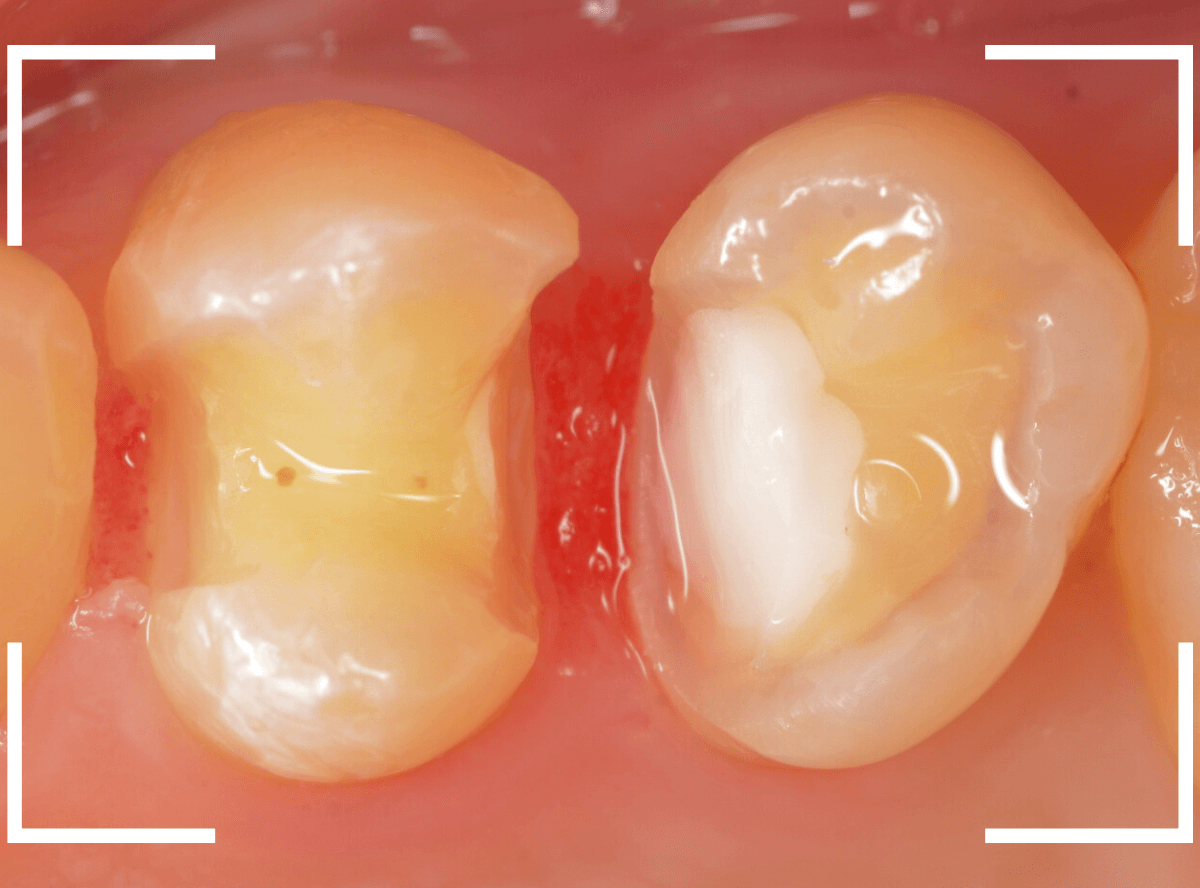

Case.29

下の奥歯が虫歯になった患者さんのケースです。

〇部が虫歯の部分です。

写真で見てわかるように、常に舌が歯に触っているような状況です。

このような場合、虫歯を見つけづらいですし、治療の難易度もあがります。

虫歯の治療を開始します。

隣の歯とのすき間を中心に広い虫歯になっていました。

虫歯治療後、特に症状もなく経過観察できましたので、つめものを作る治療に入ります。

セラミック治療をご希望されましたので、

小臼歯をE-MAX・インレー、

大臼歯をジルコニア・インレーで処置することになりました。

治療後の状態です。

自然な仕上がりで、患者さんにもご満足いただけました。